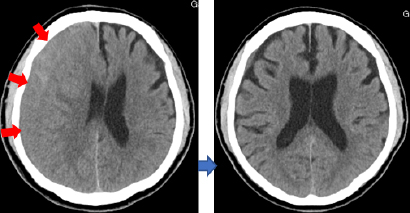

慢性硬膜下血腫に対する穿頭洗浄術

頭部外傷後、脳の表面に少しずつ血腫が形成されることがあります。「慢性硬膜下血腫」という疾患であり、頭部外傷後1、2ヶ月してから頭痛や手足の麻痺、もの忘れを中心とした認知症様症状などが出現します。治療は、局所麻酔下に頭蓋骨に約1cmの穴をあけ、貯留している古い血腫を除去します。多くの場合後遺症を残さず治癒しますが、10-20%で再発(血腫が再貯留)し、再手術が必要になることがあります。

頭部打撲後しばらくして、硬膜と脳の間に血腫が形成されました(赤矢印)。穿頭血腫除去術により血腫を除去しました。